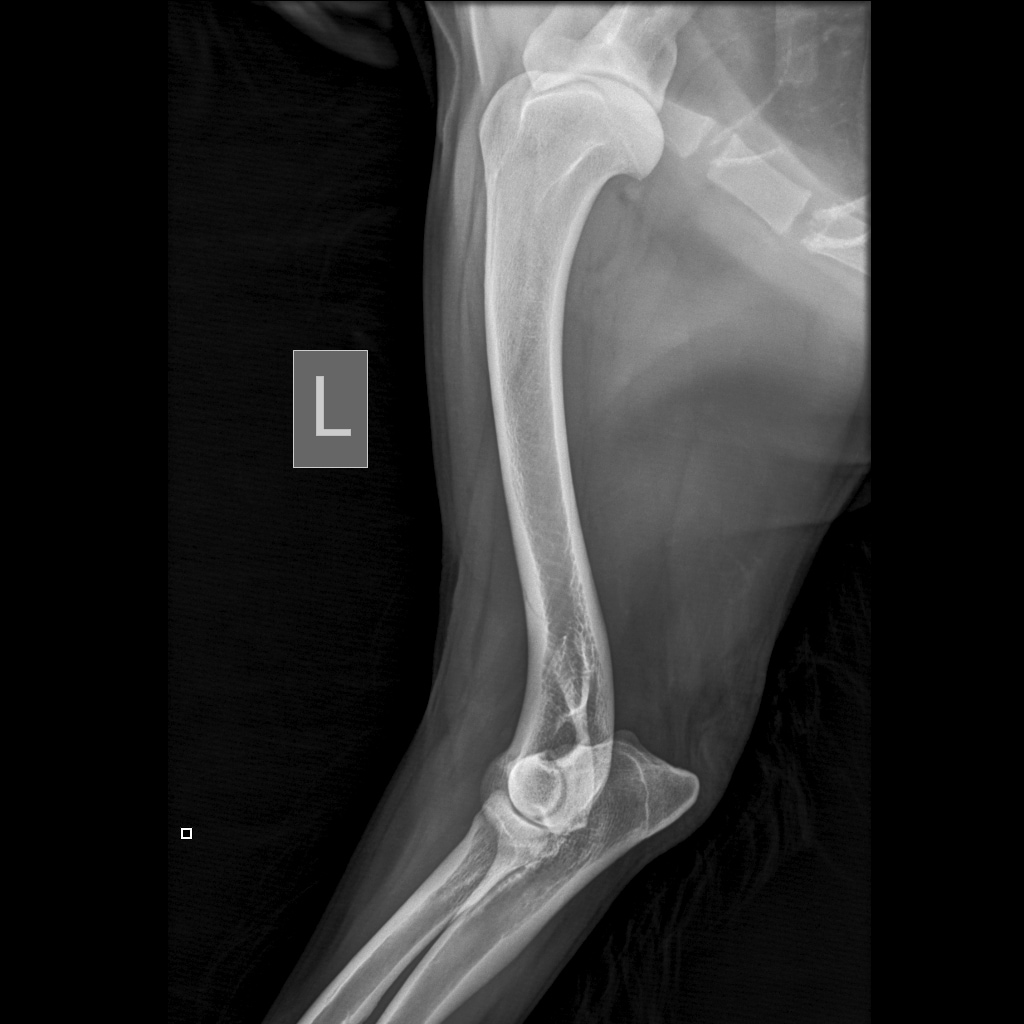

Вчера резко захромал, встал на 3 ноги и понос.

По рентгену чисто

В понедельник КТ